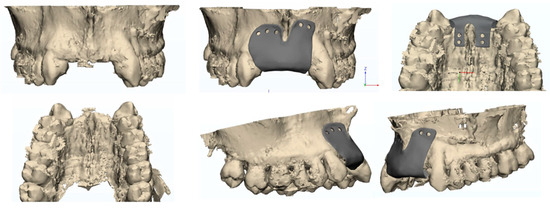

The design and creation of the custom-made membrane (Figure 1) involved a fully digital workflow that began with the previous implant placement planning.

Specifically, the CAD (Computer-Aided Design) 2024 software allows visualization of the 3D virtual model of the patient’s jaws, the digital diagnostic wax-up, and the planned implant position and number. The dental technician team and the dentist could actively collaborate using the software to decide on the most suitable characteristics for the patient. A 3D modeling software 3D CREO Parametric PTC (v.10) has been used.

The prosthetic project played a crucial role in order to choose the correct the height of the mesh. Specifically, the position of the dental elements, pre-visualized through digital wax-up, was used to determine the amount of bone height to be regenerated.

Then the CAD modeling software was utilized to design the mesh.

A mesh thickness ranging from 0.2 to 0.7 mm was used for all patients.

A total of 4 occlusive membranes and 6 membranes with a perforated surface were used.

Once the design was approved, the mesh was fabricated from surgical-grade titanium using Selective Laser Melting technology. The membrane was then cleaned, sterilized, and sealed to prevent any contamination before the procedure.

Figure 1. Final design of custom-made mesh.